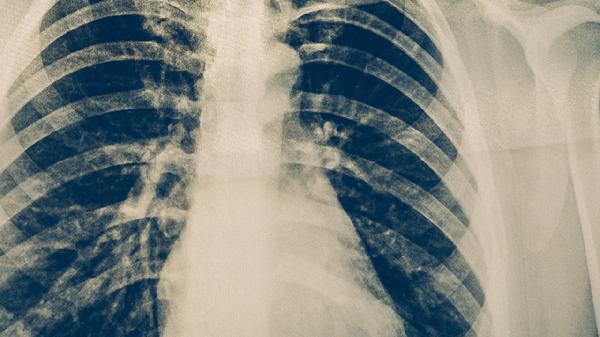

肺结核治疗需坚持6-8个月规范用药,期间出现副作用应及时与主治医生沟通调整方案。保持高蛋白饮食如鸡蛋、鱼肉有助于修复组织损伤,适当补充复合维生素可改善药物导致的营养素消耗。避免与酒精、油腻食物同服减少肝脏负担,治疗期间每1-2个月需复查胸片评估疗效。若出现严重过敏或黄疸应立即停药并急诊处理。